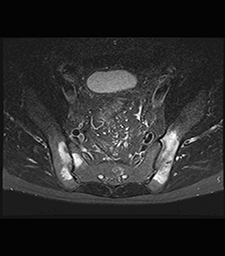

IRM des articulations sacro-iliaques

Cet examen est indiqué essentiellement dans la recherche d’une inflammation aigue ou chronique de cette articulation, appelée sacro illite.

Plusieurs pathologies peuvent être responsables de cette inflammation et notamment la spondyloarthrite ankylosante (SPA). L’IRM est l’examen le plus précis pour la recherche de cette inflammation